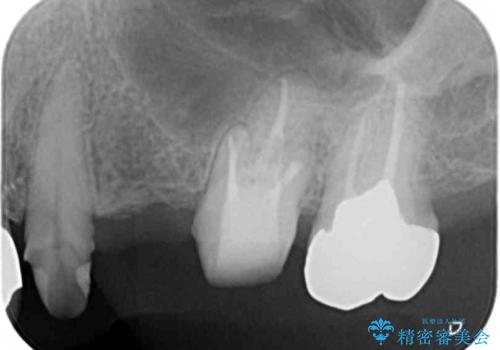

- 長年使用し、見た目の気になってきた金属製のブリッジのやりかえを希望され来院されました。

老朽化した金属製のブリッジを丁寧に除去したのち、金属を用いない審美性の高いセラミック製のブリッジでのやりかえを計画します。